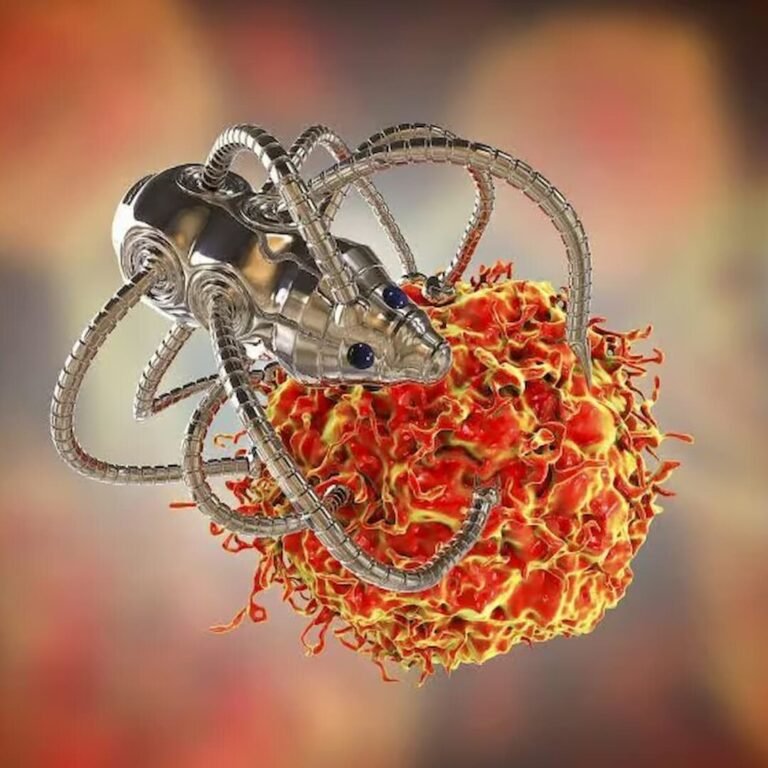

promete revolucionar el tratamiento contra el cáncer. Actualmente, la quimioterapia convencional afecta tanto a células cancerígenas como...

está transformando el panorama del tratamiento contra el cáncer. Estos innovadores fármacos, diseñados para reconocer simultáneamente dos...